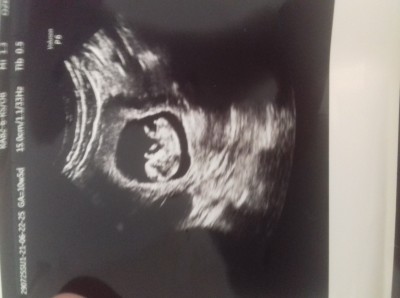

image hanimlar 11 haftalik gebeyim doktor cikinti var %70 erkek dedi resimdede belirgin sekilde cikinti gorunuyor sizce dogrumudur

Gebelik haftası 11

11+5 de cikinti var  erkek gibi ama sonraki.kontrolde emin olalim dedi erkekmis burdada var gibi cikinti canim

Oyle mi ben de 1 er hafta arayla gttm ikisndede cikinti gitmemis var dedi ama kesin soyleyemem dedi bnde bakinca goruyorum cikintiyi acaba kardon falan degil midir

Cikinti var ama benimkinin durusundan dolayi kordondan olabilir demisti emin kesin demedi yani ama sonra erkek gosterdi:)